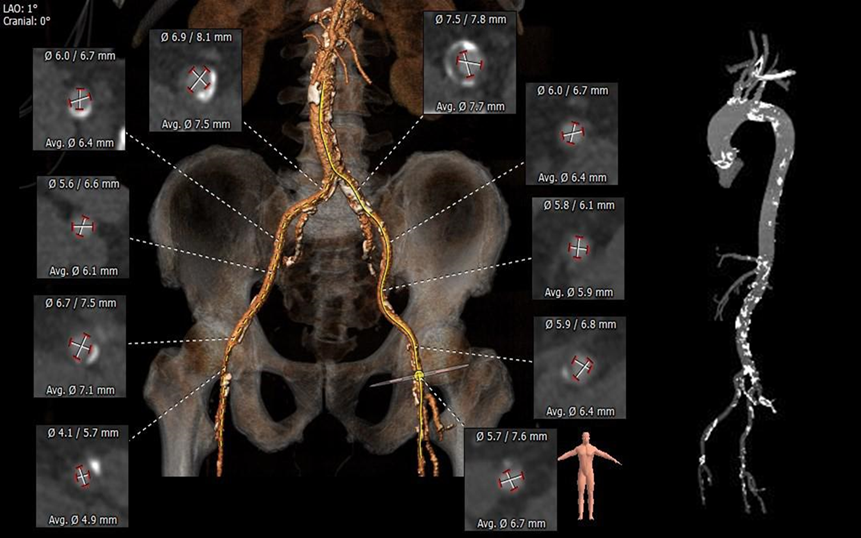

根部评估

瓣上测量

弓部及入路评估

孙志奇教授团队术前讨论,考虑患者三叶式主动脉瓣,重度钙化,钙化分布较均匀,瓣膜植入过程中有少量或少量偏多瓣周漏的可能。患者左冠开口高度略低,测量发现冠脉有病变可能,需在TAVR术前行造影观察具体情况。入路血管多发钙化,右侧股动脉腹股沟韧带远端血管纤细,左侧血管内径稍细,血管鞘及输送器通过难度稍偏高,入路血管并发症风险稍偏高。